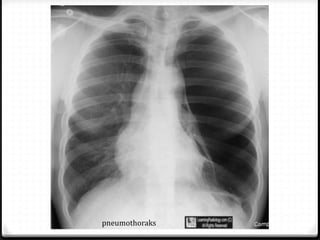

Pneumothoraks

0 Udara pada rongga pleura

0 15%–40% ditemukan pada trauma thoraks

0 Ruptur alveoli karena ada tekanan meninggi secara tiba-tiba

pada intrathorakal akibat trauma dengan atau tanpa fraktur

costae

0 Radigrafi polos >>

0 ± 10% tidak dapat dievaluasi dengan radiografi polos  CT scan

Tension pneumothoraks

Hidropneumothoraks kanan